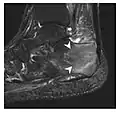

Figure 10: Calcaneal fatigue fracture in a 30-year-old male runner. Radiographs were normal (not shown). (a) Sagittal T1-weighted and (b) short tau inversion recovery images show a linear hypointensity (arrows) of calcaneal tuberosity within diffuse bone marrow edema, which appears as an ill-defined area of hyperintensity on a fluid sensitive pulse sequence (arrowheads).[1]

Fatigue fractures are more frequent in women which may be due to the relatively smaller bones of women. Moreover, pregnancy is a well-recognized risk factor for femoral neck fatigue fracture. While fibular and metatarsal fractures have a low risk of complications, other sites including the femoral neck, midanterior tibia, navicular, talar, and other intraarticular fractures are prone to complications such as delayed union, nonunion, and displacement. The site of the insufficiency fracture may be specific to the activity: for example, rugby and basketball players are more prone to navicular fractures, while gymnasts have a higher risk for talar fractures (Figure 7). Long distance runners are at increased risk for pelvic, tibial (Figures 8 and 9), and fibular fractures. In the military, calcaneus (Figure 10) and metatarsals are the most commonly cited injuries, especially in new recruits. Billiard players are at risk for upper limb fractures (Figure 11).[1]

Fatigue fractures

Fatigue fractures occur when healthy bone is exposed to repeated stress. The bone is a living tissue, with the capacity to repair itself; fatigue fractures occur when repetitive injuries exceed the repair capacity of the bone. This type of fracture does not occur as a single event but rather incrementally as a sequence of cellular events that begin with increased osteoclastic activity. Microfractures occur later and are accompanied by bone marrow edema, which can be detected on MRI. This stage appears on MRI as an isolated bone marrow edema pattern without a fracture line and is called stress reaction. Then, periosteal new bone forms and may be visible on radiography. Full cortical fractures occur if the repetitive stress continues. Only timely detection and appropriate management can interrupt this sequence.[1]